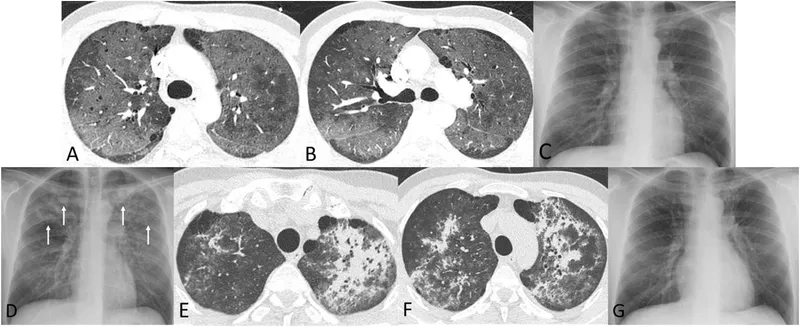

- Sx: Progressive dyspnea, non-productive cough, fever, hypoxemia.

- CXR: Diffuse bilateral interstitial infiltrates (ground-glass).

⭐ Cell membrane: cholesterol, not ergosterol → most antifungals ineffective.

- Pneumocystis jirovecii (PCP): Pneumonia in HIV (CD4 < 200); silver stain for cysts.